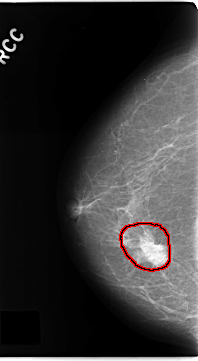

C_0181_1.RIGHT_MLO

FILE: C_0181_1.RIGHT_MLO.OVERLAY

TOTAL_ABNORMALITIES 1

ABNORMALITY 1

LESION_TYPE MASS SHAPE IRREGULAR MARGINS SPICULATED

ASSESSMENT 5

SUBTLETY 5

PATHOLOGY MALIGNANT

TOTAL_OUTLINES 1

BOUNDARY